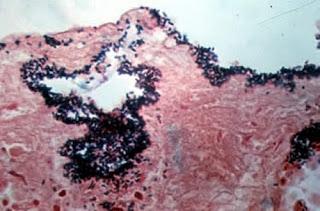

Tras la ingestión, se libera la enterotoxina dentro del tubo digestivo superiorproduciendo salida de líquido que afecta principalmente al íleon.Tras un período de incubación de 8-24 horas comienzan las náusea, dolor abdominal y diarrea. No se presenta fiebre y el vomito es poco común. Por lo general pasadas 24 horas ocurre una recuperación espontanea.En casos graves, puede producirse una enteritis necrótica y septicemia tras el consumo de una dosis importante de bacterias dando lugar a una intoxicación grave.